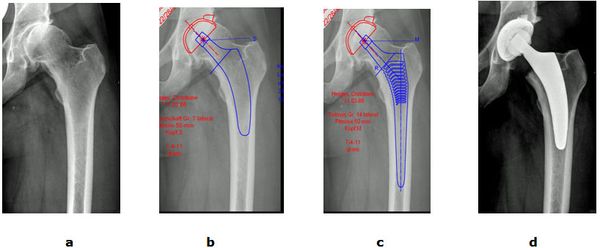

Abb. 3: Präoperative Planung zur Festlegung des Prothesentyps. Anpassung der Prothese an die Knochenform unter Berücksichtigung des richtigen Offsets (Verhältnis von Femurkopf- und Schaft) um postoperativ eine physiologische Muskel- und Bandspannung zu erreichen.

a Röntgenbild vor der Operation

b Planung 1 mit Kurzschaftprothese

c Planung 2 mit einem Standardschaft

d Umsetzung der Planung 1 mit postoperativen Röntgenbild.